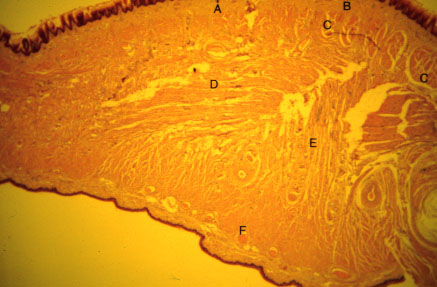

K-slide 42: Higher magnification of 41

A. Filiform papillae

B. Lamina propria

C. [Longitudinalis superioris]

D. [Transversus]

E. [Verticalis]

F. [Longitudinalis inferioris]